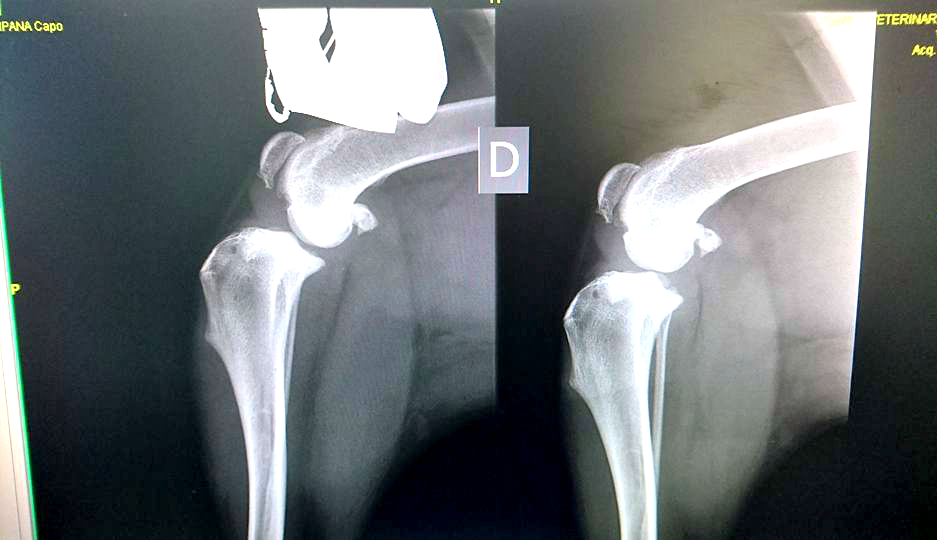

CALVATONE – Una nuova vita per lui. La seconda, in attesa di una terza che sarà al termine del tunnel in cui Capo, meticcio arrivato a ‘La cuccia e il nido’ di Calvatone, è precipitato. Una storia, la sua, come tante. Quella di chi prende un cane e poi – di fronte alle difficoltà di una convivenza – ci rinuncia. “Capo – raccontano i volontari del canile di Calvatone – è cresciuto in famiglia, e sarebbe dovuto essere così per sempre, ma qualcosa è andato storto e poche settimane fa ha fatto il suo ingresso da noi, al Canile Rifugio la Cuccia e il Nido Anpana Onlus di Calvatone. Capo è stato rinunciato dalla famiglia per presunta aggressività nei confronti della figlia. Nessun educatore, nessuno si è rimboccato le maniche, per lui c’era solo un box ad attenderlo. Capo dopo i primi giorni di disorientamento, durante i quali si disperava e tremava tutto il tempo per la paura, si è rivelato il contrario di quello che gli ex padroni avevano riferito: è un bravissimo cane dagli occhi dolci e speranzosi, con la coda perennemente in movimento per ricevere una coccola, è buono e docile con tutti i volontari e gli operatori che fin da subito l’hanno curato e amato”. Le ‘disgrazie’ però non vengono mai sole. I volontari notano in capo una difficoltà di movimento e decidono di accertarsi delle reali condizioni del meticcio ‘sorridente’. “Una persistente zoppia alle zampe posteriori, per cui sono stati effettuati alcuni accertamenti. Speravamo non fosse qualcosa di grave ma purtroppo non è stato così. Le lastre hanno evidenziato la rottura completa del crociato della zampa posteriore destra, ed il lesionamento del crociato posteriore sinistro”. Un problema, benché piuttosto serio, risolvibile. Capo va sotto ai ferri grazie alla disponibilità di Anpana a farlo curare e a quella della Clinica Sant’Eusebio di Asola disposta a venire incontro al canile con le spese – ingenti – di quel tipo di operazione. “Il 10 marzo Capo ha subito l’operazione a carico del crociato posteriore destro presso la Clinica Sant’Eusebio di Asola, e subirà un ulteriore intervento al crociato sinistro nei prossimi mesi. La prima operazione (Osteotomia piatto tibiale con lama 22,5 mm, rotazione piatto tibiale, fissazione con placca TPLO 3,5 mm 6 fori, sutura cute e sottocute e bendaggio di Robert Jones, ndr) è andata a buon fine, ora Capo dovrà restare a riposo”. Operazione, lastre e controlli sono costati 900 euro. Tutti sostenuti da Anpana. “Non potevamo non intervenire – spiega Patrizia Storti di Anpana – e così abbiamo deciso di procedere. La clinica ci ha fatto un prezzo di favore, lo staff è stato molto disponibile e di questo li ringraziamo enormemente. A favore di Capo e delle sue cure si è deciso di creare una raccolta fondi. Come ben sapete le spese qua in canile sono davvero tante, le rinunce di proprietà e gli abbandoni continuano e i cani che arrivano hanno spesso bisogno di analisi e cure mediche costose”. Per Capo – il meticcio sorridente – si è aperta una raccolta. Diverse le strade che possono consentire un aiuto al meticcio: l’adozione a distanza, il versamento di una donazione sul c/c presso la Banca CARIPARMA di San Giovanni in Croce, IBAN: IT 25 N 06230 57130 000043318875 – Causale: Donazione pro Capo, una donazione PayPal cliccando sul pulsante “fai una donazione” sulla nostra pagina facebook (questo metodo è totalmente sicuro ed affidabile, nonché facile e veloce, accetta tutte le carte di credito, anche PayPal si può utilizzare anche dall’estero), l’iniziativa “Un Uovo per Fido” con cui si possono sostenere le cure di Capo attraverso le uova solidali al cioccolato al latte o fondente che si possono trovare presso l’Ufficio del Canile Rifugio tutti i giorni dalle 14 alle 18, weekend compreso. Capo avrà una seconda possibilità in questa sua seconda vita. In attesa di una terza, magari al caldo di una casa con una famiglia dal cuore grande, disposta a prendersene cura.